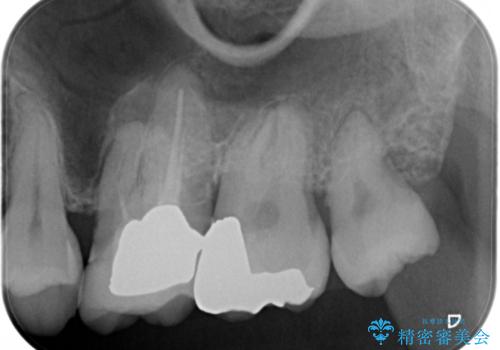

セラミックインレー 虫歯で欠けた歯の治療